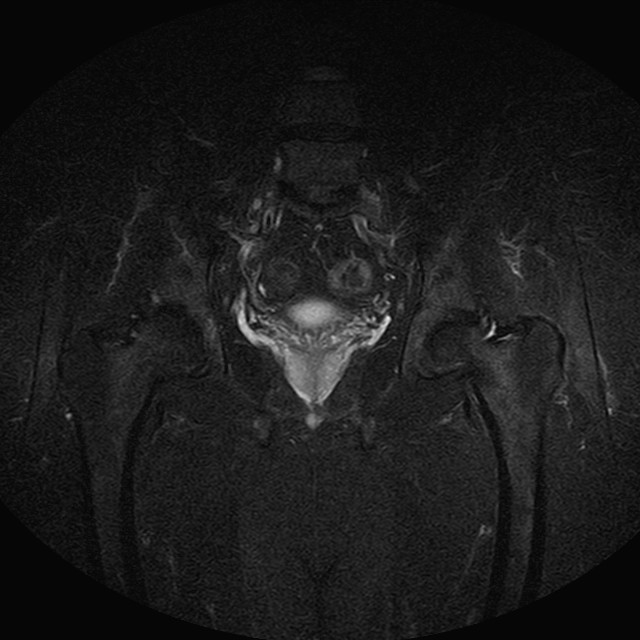

Esami: RMN BACINO

eSTIR

Evidenti e simmetriche alterazioni osteofitosiche in regione coxo femorale con riduzione delle rime articolari. Degenerazione completa del cercine glenoideo. Non attuali segni di versamento articolare. Non segni di edema osseo che escludono attuale algodistrofia od osteonecrosi. Lieve e simmetrica riduzione del trofismo della muscolatura glutea.